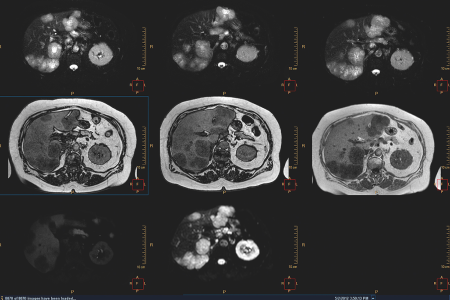

Die Entwicklung in der Krebsversorgung geht zu optimierten, personalisierten Behandlungsmöglichkeiten, die für jeden Patienten maßgeschneidert sind. Alle Informationen aus den Fachbereichen der Krebsdiagnose und Genomik werden zur Entscheidungsfindung durch Krebsspezialisten in der Diagnosephase zusammengeführt. Die Digitalisierung im Gesundheitswesen macht es möglich, alle Diagnosedaten (aus Radiologie, Pathologie und In-vitro-Diagnostik) in digitaler Form bereitzustellen.

Philips kann Under- und Overstaging reduzieren und so die zuverlässige Charakterisierung und das zuverlässige Staging der Erkrankung eines Patienten ermöglichen.

Fortschrittliche Visualisierungs-Tools für die Onkologie zur Beurteilung des Krankheitsstadiums und des Ansprechens auf die Behandlung

Umfassende Ultraschalllösungen zur Beurteilung und Überwachung von Brust, Leber und Prostata